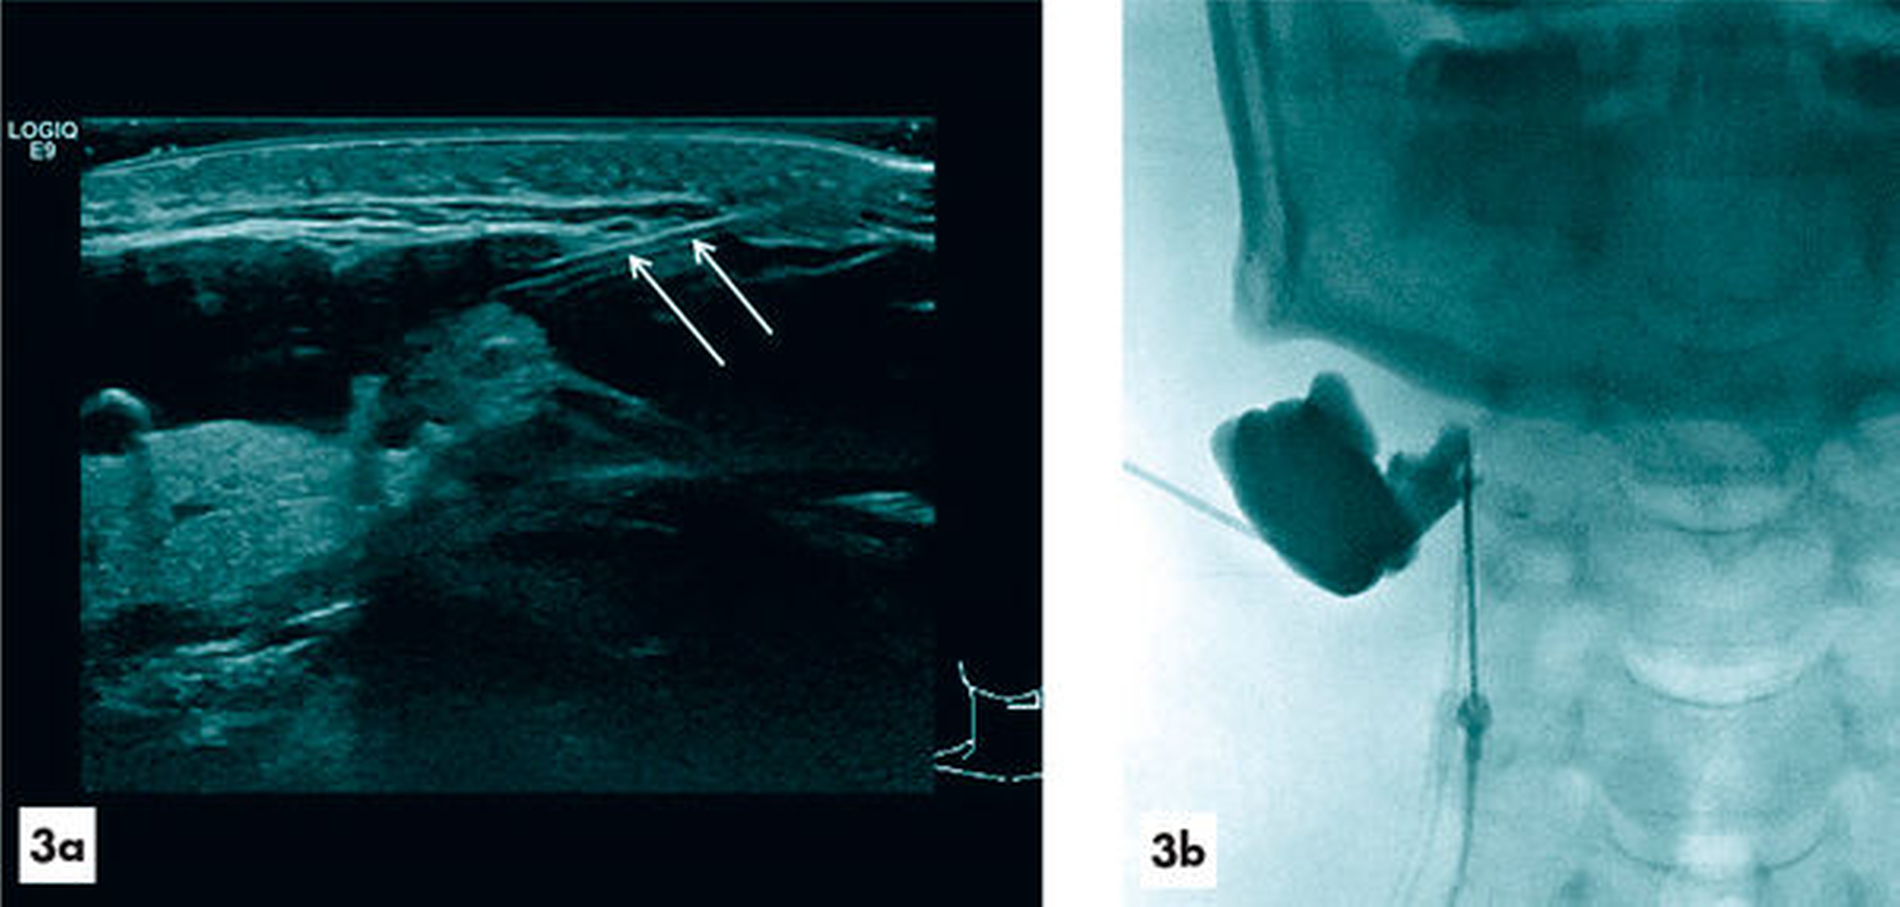

Im Oktober 2018 erfolgte im Universitätsklinikum Regensburg erstmalig die sonografisch gesteuerte Punktion der echoarmen, zystischen Raumforderung, wobei sich eine klare, schleimig-zähe Flüssigkeit aspirieren ließ (Abbildung 3). Wegen der schleimigen Konsistenz der Flüssigkeit, die gegen das Vorliegen einer zu diesem Zeitpunkt nicht infizierten und nicht eingebluteten lymphatischen Malformation sprach, wurde das asservierte Sekret in den Instituten für klinische Chemie und Laboratoriumsmedizin sowie für Pathologie des Universitätsklinikums Regensburg laborchemisch und histopathologisch untersucht. Es wurde als makrophagenreiches Zystenpunktat mit geringgradig neutrophilen Granulozyten und wenigen Lymphozyten gewertet, wodurch die Diagnose einer lymphatischen Malformation eher ausgeschlossen und stattdessen die Verdachtsdiagnose einer Retentionszyste beziehungsweise Tauchranula erhärtet werden konnte.